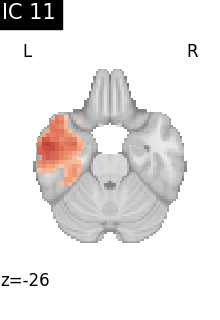

Finally, we plot the map for each ICA component separately

from nilearn.image import iter_img

from nilearn.plotting import plot_stat_map, show

for i, cur_img in enumerate(iter_img(canica_components_img)):

plot_stat_map(

cur_img,

display_mode="z",

title=f"IC {int(i)}",

cut_coords=1,

vmax=0.05,

vmin=-0.05,

colorbar=False,

)

show()